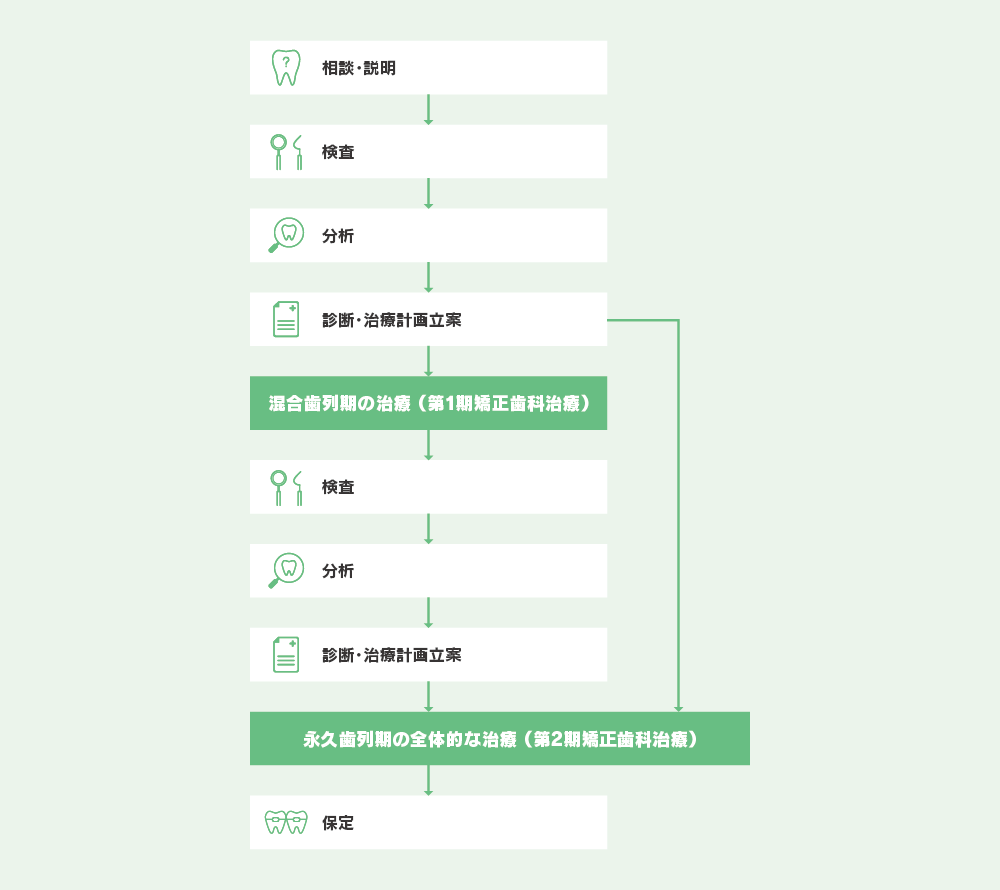

小児矯正には、「第一期治療」と「第二期治療」があります。

「第一期治療」では、永久歯がきれいに生えるように、あごの成長をコントロールします。受け口や出っ歯の改善、上下のあごのバランスを整えることを目指します。また、口呼吸や指しゃぶり、舌の癖などを早い段階で改善します。

「第二期治療」は、永久歯が生えそろった後に行います。ブラケットとワイヤーを使った治療で、基本的には大人の矯正治療と同じです。

治療の進め方と費用

患者さまのお悩みについて十分に話し合い、治療について検討していただいたうえで、治療を始める決心がついたら精密検査に進みます。検査では歯型を取ったり、顔や口の写真やレントゲンを撮影して診察を行います。検査結果に基づいた治療方針の詳細をご説明し、納得していただいてから治療を開始します。

装置を装着した後は、歯の動きに合わせてワイヤーやパワーチェーンなどを違和感がないように調整します。その後は、きれいな歯並びを保つために保定装置(リテーナー)を使用して、長期的に治療を行います。

01.子供の矯正歯科治療の進め方